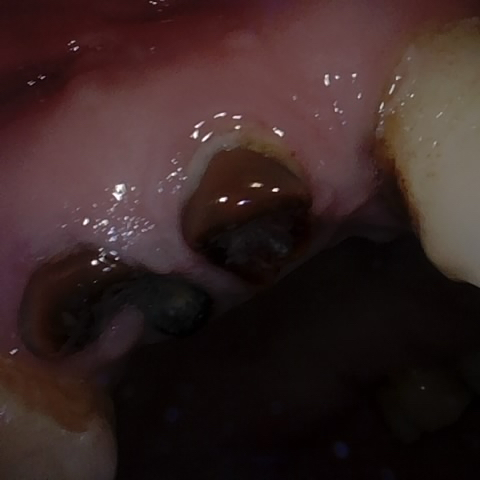

Image 1408 / 1743

NHD36692

Annotated as "Good"

Original Image Rendering Image